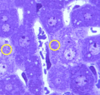

what are the small structures collected within the yellow circles in these hepatocytes?

mitochondira